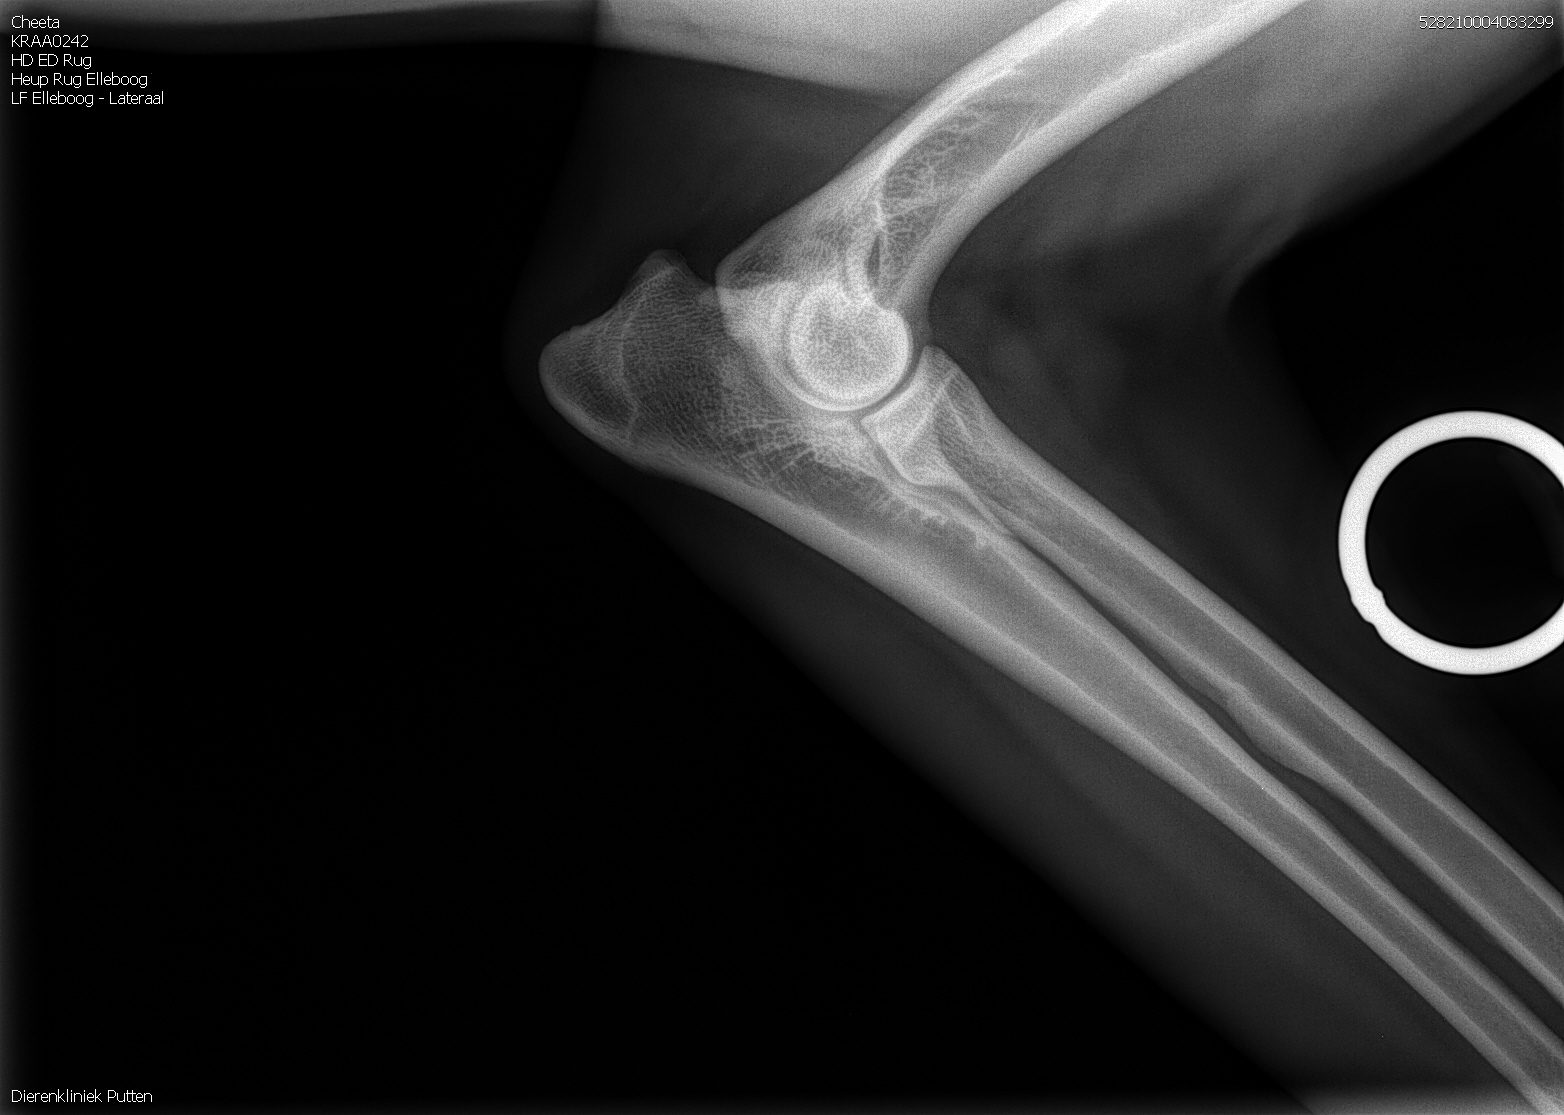

HD: A

ED: vrij